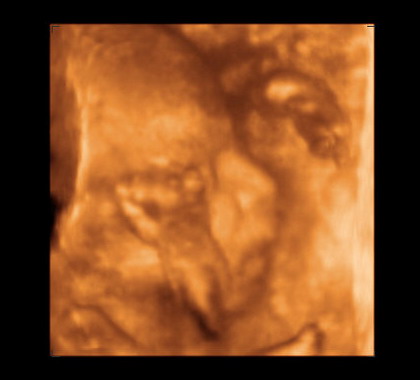

4D-set várjuk nagyon! Jajj, nekem olyan nagy élmény volt!!!